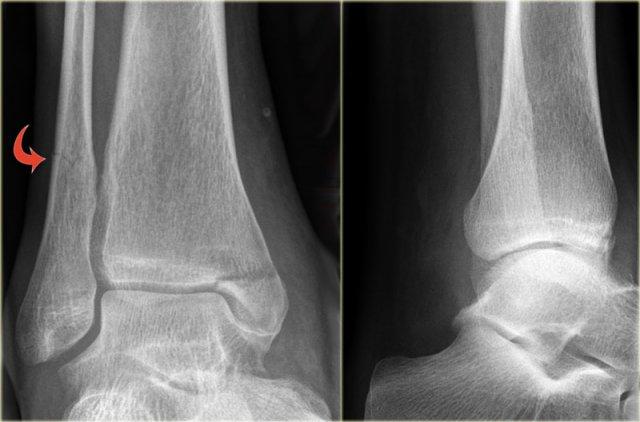

Stage 2

Giai đoạn 2 không phổ biến và dễ phát hiện.

Lực khép lớn hơn dẫn đến mắt cá trong bị đẩy ra theo chiều dọc hoặc chéo.

Giai đoạn 2 không vững vì vòng cổ chân bị gãy ở hai vị trí.

Lưu ý hướng nằm ngang của gãy mắt cá ngoài và hướng thẳng đứng của gãy mắt cá trong.

Những lực cực lớn hẳn đã đẩy bật mắt cá trong ra.